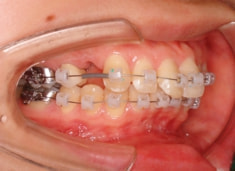

治療開始から1年7ヶ月後